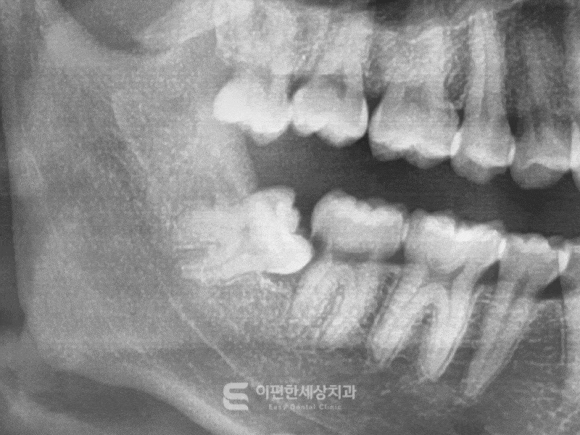

촬영일자 : 2024. 02. 16

※이해를 돕기 위한 참고용 이미지입니다.

하치조신경은 아래턱뼈 안쪽을 지나가는

아주 중요한 신경입니다.

이 신경은 아래쪽 치아부터 해서 입술과 턱 부위의

감각을 담당하고 있죠.

이런 하치조신경과 사랑니의 뿌리가

매우 가까이 위치해 있다면

발치 과정에서 신경에 자극이 전달될 가능성이 생기는데요.

신경과의 거리가 지나치게 가깝고

뿌리 형태가 복잡하거나, 검진 결과상으로도

위험도가 높다고 판단되는 경우에는

조심스럽게 접근해야겠지만, 이런 경우라고 해도